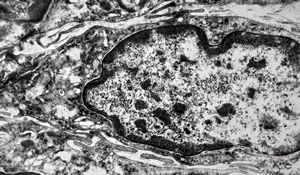

F,41y. | synovial metaplasia - capsule of implantate

F,41y. | synovial metaplasia - capsule of implantate

F,41y. | synovial metaplasia - capsule of implantate

F,41y. | synovial metaplasia - capsule of implantate

F,41y. | synovial metaplasia - capsule of implantate

F,41y. | synovial metaplasia - capsule of implantate

F,41y. | synovial metaplasia - capsule of implantate

F,41y. | synovial metaplasia - capsule of implantate

F,41y. | synovial metaplasia - capsule of implantate